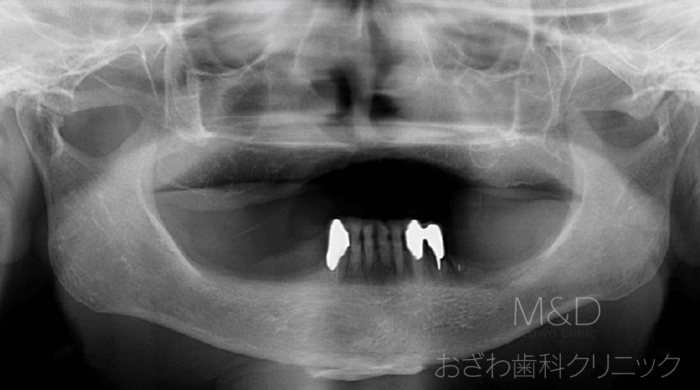

審美的で綺麗な歯をお作りできます。審美治療向けのインプラントのご紹介です。

前歯2本を失っていてしまいましたが、入れ歯ではなくご自身の歯のように美しい見た目の審美インプラント治療も行ております。…